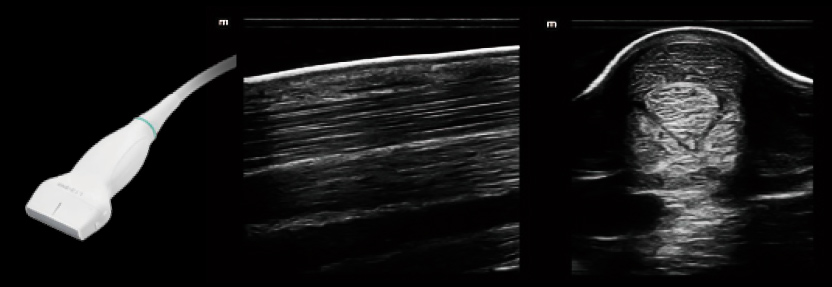

Our premium ultrasound systems can be applied to identifying horse obstetrics and genital diseases, heart diseases, and sports injuries such as tendonitis. Various transducer options are available, including linear transducers, convex transducers ,and phased array transducers. The portable ultrasound systems also offer more flexibility for veterinarians while diagnosing different diseases.

Vetus EQ

Equine Ultrasound Image System

Comprehensive Application

MSK Abdomen Reproduction

L13-3Ns C5-1s 6LE5Vs